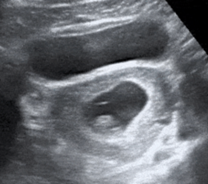

The yolk sac appears as an additional anechoic round structure with an echogenic border located within the gestational sac as in the photo below. Identification of a yolk sac definitively confirms an intrauterine pregnancy.

The fetal pole is a thickening along the wall of the yolk sac and corresponds to the early fetus. When it is developed enough (typically around 5 mm in length) the fetal pole will show a ‘cardiac flicker’.